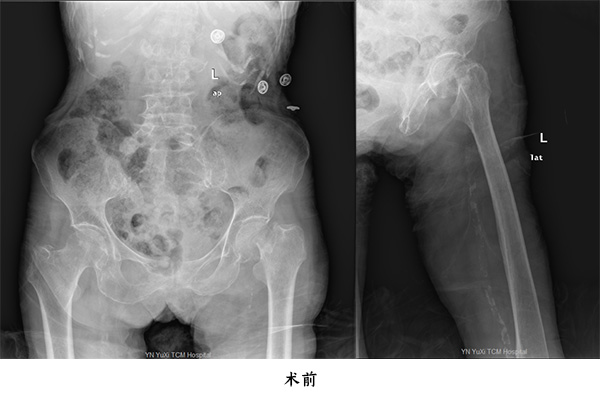

第一位為百歲老人張老太,因為在家中走路時跌倒致傷左髖部,傷后至當?shù)蒯t(yī)院就診,拍片檢查結果示左股骨頸骨折,后轉至我院住院治療;第二位百歲老人為王大爺,也是因為在家門口走路跌倒致傷右髖部,在當?shù)蒯t(yī)院就診拍片并診斷為右股骨頸骨折,后轉至我院住院治療。

由于高齡老人往往基礎病較多,全身器官如心、腦、肺等功能欠佳,如果施行手術風險極高,如果在病人管理上某一個環(huán)節(jié)出現(xiàn)問題就會隨時危及生命,高齡股骨頸骨折患者,如果采用保守治療,因為長期臥床而產生一些致命性的并發(fā)癥,入住玉溪市中醫(yī)醫(yī)院骨傷二科(關節(jié)與運動醫(yī)學科)后,經科室團隊詳細制定治療計劃,麻醉科會診,分別于2020年12月8日及2020年12月4日為兩名百歲老人施行人工股骨頭置換手術,手術過程順利,通過該手術,兩名百歲老人再次站起來下地步行,均順利康復出院。